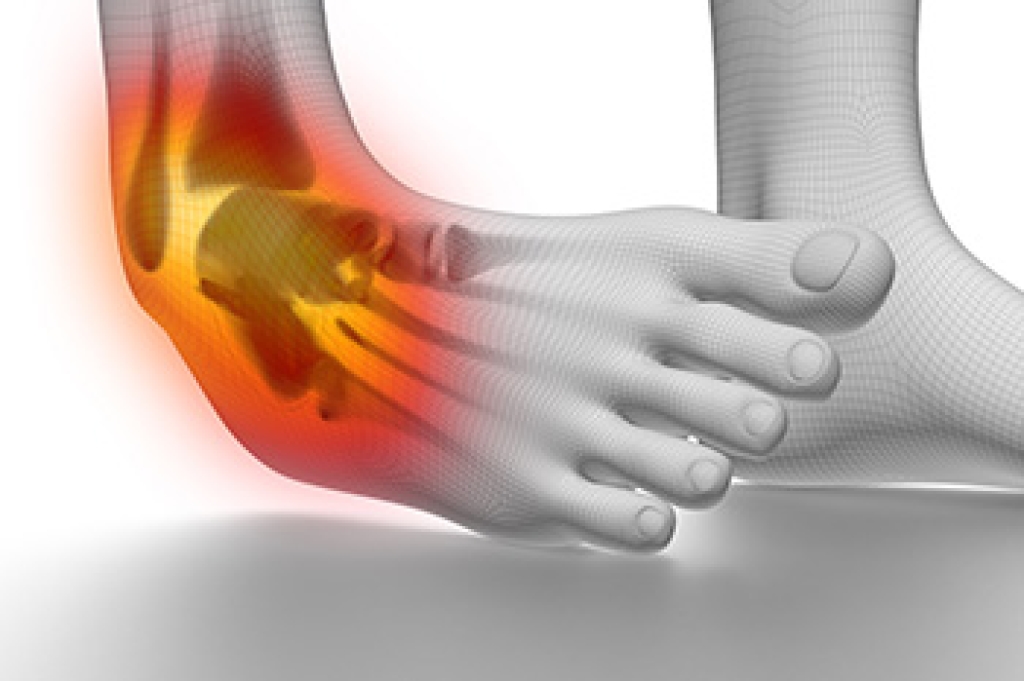

Ankle sprains occur when the ligaments that support the ankle are stretched or torn, often due to a sudden twist, fall, or misstep on uneven surfaces. This injury is common in sports and daily activities that involve quick changes in direction. Ankle sprains are classified into three grades. A mild sprain, or Grade 1, involves slight stretching of the ligament, while a moderate sprain, or Grade 2, includes partial tearing and more noticeable swelling. A severe sprain, or Grade 3, means the ligament is fully torn, leading to significant instability. Symptoms can include pain, swelling, bruising, and difficulty walking. A podiatrist can evaluate the injury, recommend the appropriate treatment, and provide supportive devices to promote proper healing. If you have sprained your ankle, it is suggested that you promptly contact a podiatrist who can accurately diagnose and treat ankle sprains.

Ankle sprains take place when the ligaments in your ankle are torn or stretched beyond their limits. There are multiple ways that the ankle can become injured, including twisting or rolling over onto your ankle, putting undue stress on it, or causing trauma to the ankle itself.

Treatment of a sprain depends on the severity. Many times, people are told to rest and remain off their feet completely, while others are given an air cast. If the sprain is very severe, surgery may be required.

If you have suffered an ankle sprain previously, you may want to consider additional support such as a brace and regular exercises to strengthen the ankle.